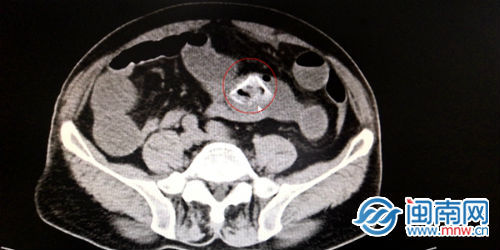

8月21日,吴老汉被转入第909医院继续治疗。在进一步完善相关检查的基础上,该院消化内科和普通外科的值班人员组织了紧急会诊,结果发现患者的小肠内有一个高密度的异物,因其肠道内有多个呈凹陷状的憩室,而异物不偏不倚地卡在了其中的一个憩室里动弹不得,从而将整个肠道都死死地堵住了。

考虑到常规的肠镜方式够不着异物,加上异物已经在患者体内存留了数天,若采取保守治疗的方法可能会引发肠道穿孔、出血等诸多风险。在综合上述各种因素后,医务人员在征得患者及其家属同意的情况下,决定以外科手术的方式实施剖腹探查来将异物取出。术中,医务人员先在发现小肠异物的部位将肠管切开,然后取出了一粒开始糜烂的异物,剥开后证实是菠萝蜜核,紧接着是对肠腔的内容物一一清理排空。